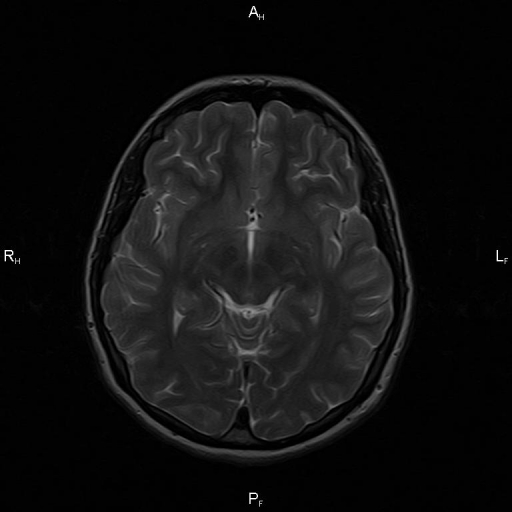

Аномалия Арнольда-Киари: MRI снимки